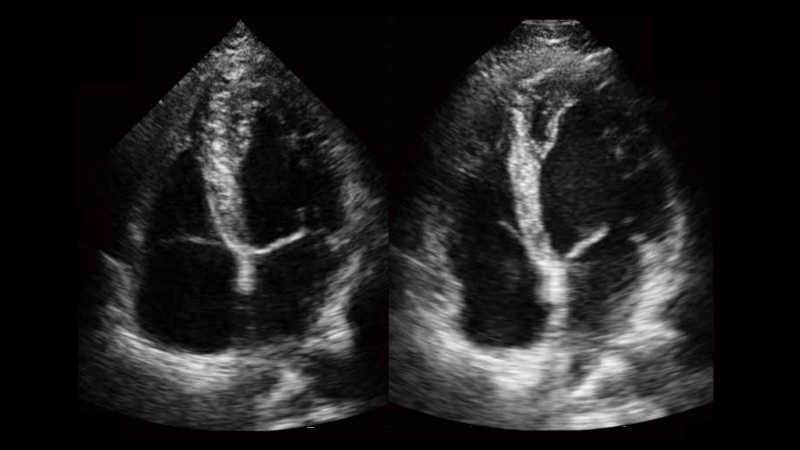

自動識別收縮和舒張末期心肌內膜,自動計算射血分數EF值。